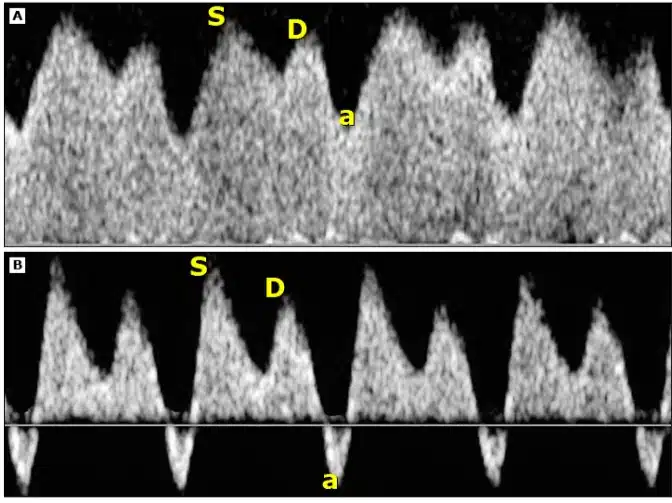

Abaixo, tem-se uma comparação da Dopplervelocimetria do ducto venoso em fetos apropriados para a idade gestacional e severamente restritos ao crescimento. Na imagem (A), tem-se um doppler de ducto venoso em um feto AIG. Enquanto que na imagem (B), uma relação cérebro-placentária (RCF) grave com 27 semanas de gestação. Observe que a onda “a” aparece invertida, o que indica uma grave restrição do crescimento fetal.